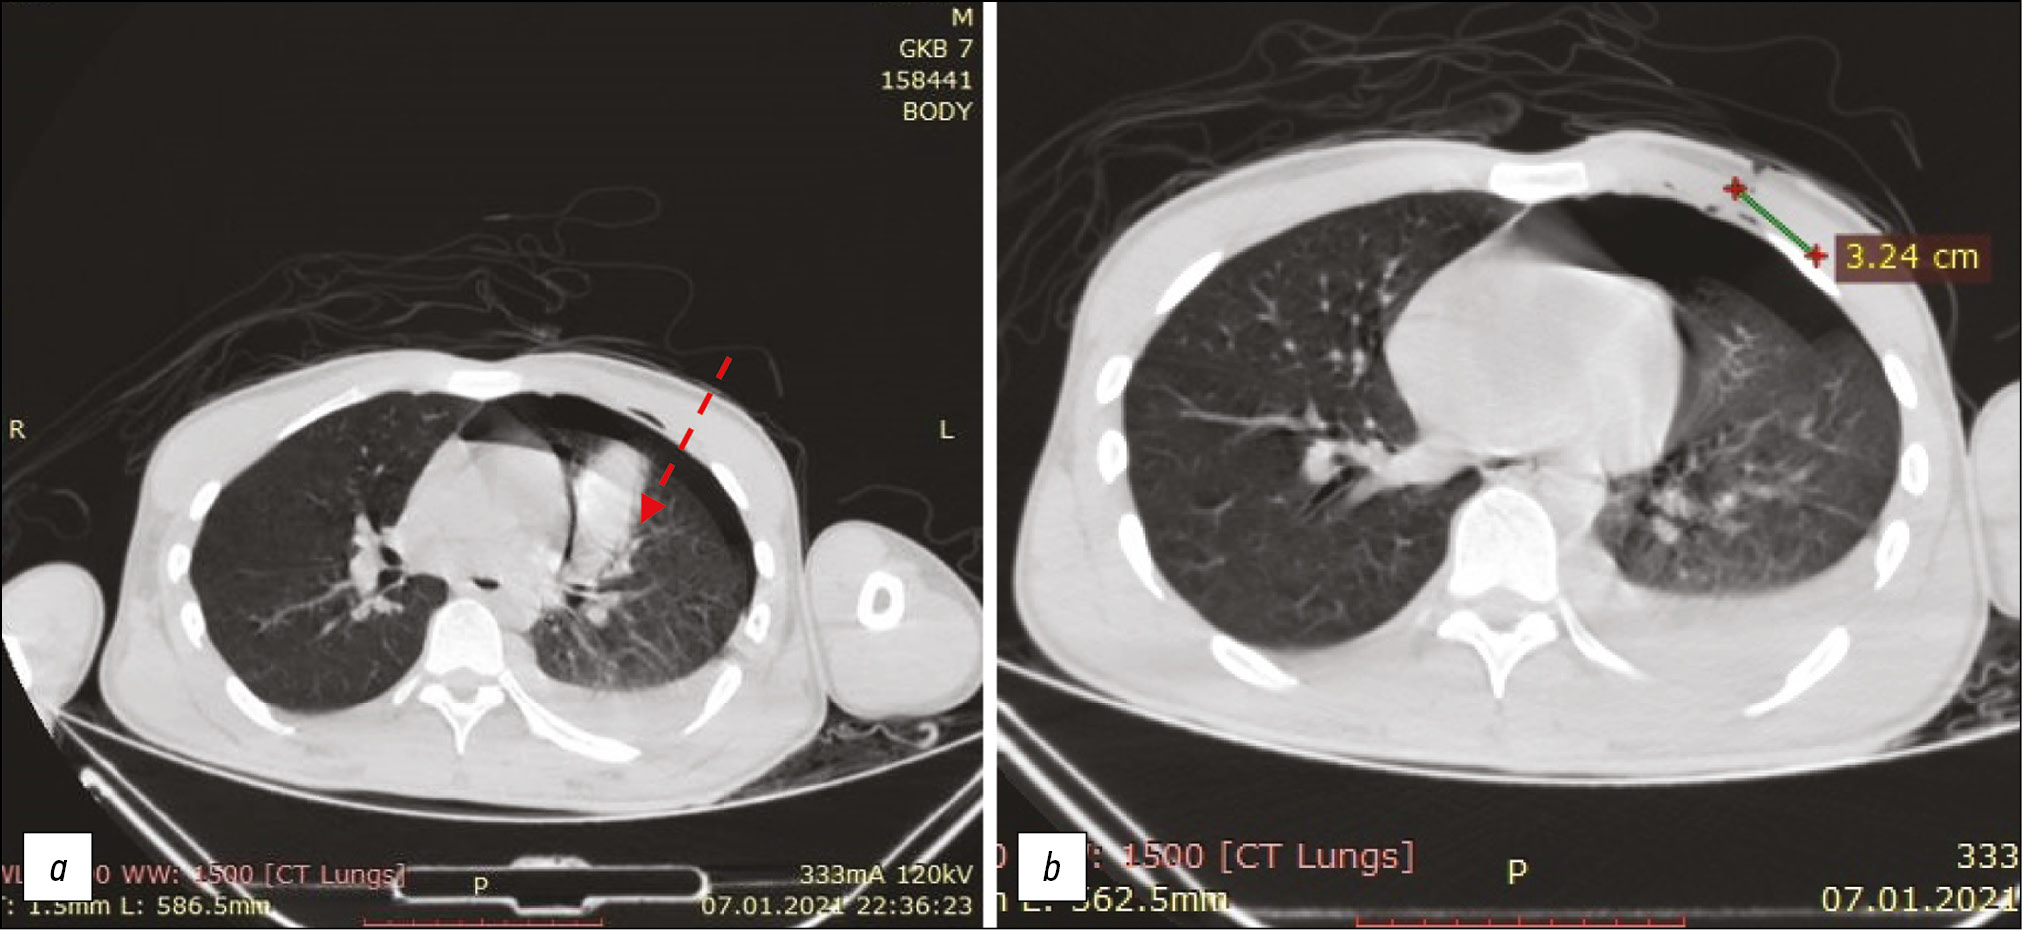

- рана в правом гипогастрии (уровень 287 мм): раневой канал проникает в брюшную полость, направлен слева направо и спереди назад, повреждает восходящую ободочную кишку и правую ободочную артерию (рис. 1, а);

- рана в мезогастрии ― слева и выше пупка (уровень 349 мм), проникающая в брюшную полость: раневой канал направлен снизу вверх, спереди назад и слева направо, повреждая левую долю печени (рис. 1, b);

Рис. 1. Направление и особенности раневых каналов колото-резаных повреждений по данным компьютерной томографии потерпевшего М.: а ― проникающее повреждение брюшной полости справа (стрелка); b ― проникающее повреждение брюшной полости в мезогастрии (стрелка). / Fig. 1. The direction and features of the wound channels of stab wounds according to computed tomography studies of the victim M.: а ― penetrating damage to the abdominal cavity on the right (arrow); b ― penetrating damage to the abdominal cavity in the mesogastrium (arrow).